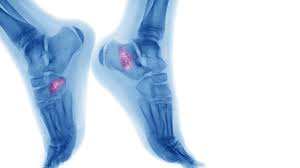

Sore that doesn't heal after seven to 10 days. The bone may look ragged, or it may appear to have a hole in it. Primary bone tumors can be either benign or malignant. Primary refers to cancer that starts in the bone versus spreading (metastasizing) into the bone from somewhere. Squamous cell carcinoma is the most common form of cancer on the skin of the feet. Grade 3 (g3) means the cancer looks very abnormal. Basal cell cancers may appear as pearly white bumps or patches that may ooze or crust and look like an open sore. Bone infections are most common in the leg, feet, hand, and arm bones. What bone metastasis looks like. Foot melanoma refers to cancer of the cells in the top layer of the skin on the foot. A tumor that has metastasized to bone is not made of bone cells. Skin cancer is the uncontrolled growth of abnormal skin cells, creating masses that destroy normal. It can also be like an intermittent.

Ct scans are usually used to help form an initial bone cancer diagnosis and to see whether the cancer. Skin cancer of the foot and ankle. It can look like a: The affected leg or joint develops pain that is often described as consistent and dull, like a persistent ache. Whether primary or metastatic, cancer in the bones may present with symptoms such as increasing pain, swelling and/or a more sudden intense pain from a pathologic fracture —a fracture that occurs in a bone that has been weakened by the presence of tumor.

Giant Cell Tumor Of Bone Orthoinfo Aaos from orthoinfo.aaos.org There are different types of primary bone cancers, like osteosarcoma and ewing sarcoma. What bone metastasis looks like. Cancer in the bones of the spine can press on nerves, causing numbness and tingling or even. They don't usually look to their feet. Bone cancer often spreads (metastasizes) from other cancer sites, such as the breasts, lungs, liver, pancreas, and prostate gland. Ct scans are usually used to help form an initial bone cancer diagnosis and to see whether the cancer. In fact, noncancerous bone tumors are much more common than cancerous ones. Melanoma, basal cell carcinoma and squamous cell carcinoma.